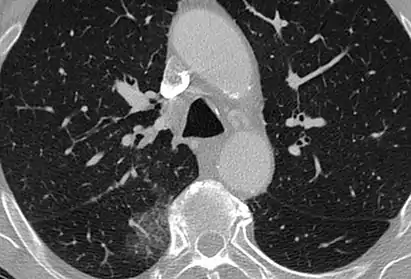

CT showing diffuse ground-glass opacities in periphery of both lungs in patient with COVID-19.

Ground-glass opacity is among the most common imaging findings in patients with confirmed COVID-19.[16][17] One systematic review found that among patients with COVID-19 and abnormal lung findings on CT, greater than 80% had GGOs, with greater than 50% having mixed GGOs and consolidation.[16] GGOs with mixed consolidation has most often been found in elderly populations.[18] Several studies have described a pattern among initial, intermediate, and hospital discharge imaging findings in the disease course of COVID-19. Most commonly, initial CT imaging reveals bilateral GGOs at the periphery of the lungs. During initial stages, this is most often found in the lower lobes, although involvement of the upper lobes and right middle lobe has also been reported early in the disease course.[16][18] This is in contrast to the two similar coronaviruses, SARS and MERS, which more commonly involve only one lung on initial imaging.[19][20] As the COVID-19 infection progresses, GGOs typically become more diffuse and often progress to consolidation.[11][18] This is sometimes accompanied by the development of a crazy paving pattern and interlobular septal thickening.[18] In many cases the most severe pulmonary CT abnormalities occurred within 2 weeks after symptoms began.[17] At this point, many individuals begin showing resolution of consolidation and GGOs as symptoms improve. However, some patients have worsening symptoms and imaging findings, with further increase in septal thickening, GGOs, and consolidation. These patients may develop lung "white-out" with progression to acute respiratory distress syndrome (ARDS) requiring treatment escalation.[17][21]

Preliminary reports have shown many patients have residual GGOs at time of discharge from the hospital. Due to the novelty of COVID-19, large studies investigating the long-term pulmonary CT changes have yet to be completed. However, long-term pulmonary changes have been seen in patients after recovery from SARS and MERS, suggesting the possibility of similar long-term complications in patients who have recovered from acute COVID-19 infection.[22]